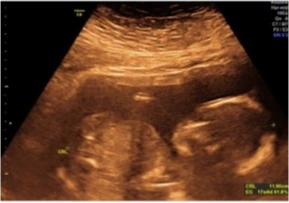

Ecografía Obstétrica

Esta ecografía sirve para medir al bebé y llevar un control de su peso y medidas, además se puede apreciar el sexo desde la semana 17 si el bebé se encuentra en posición adecuada para su visualización.

Ecografía Obstétrica 3D/4D

Este estudio incluye la ecografía obstétrica, que revisa la anatomía del bebé y llevar un control de su peso. Se busca visualizar la carita del bebé. No requiere preparación previa.

Ecografía Obstétrica 5D

Este estudio incluye la ecografía obstétrica, que revisa la anatomía del bebé y llevar un control de su peso. Se busca visualizar la carita del bebé. No requiere preparación previa.